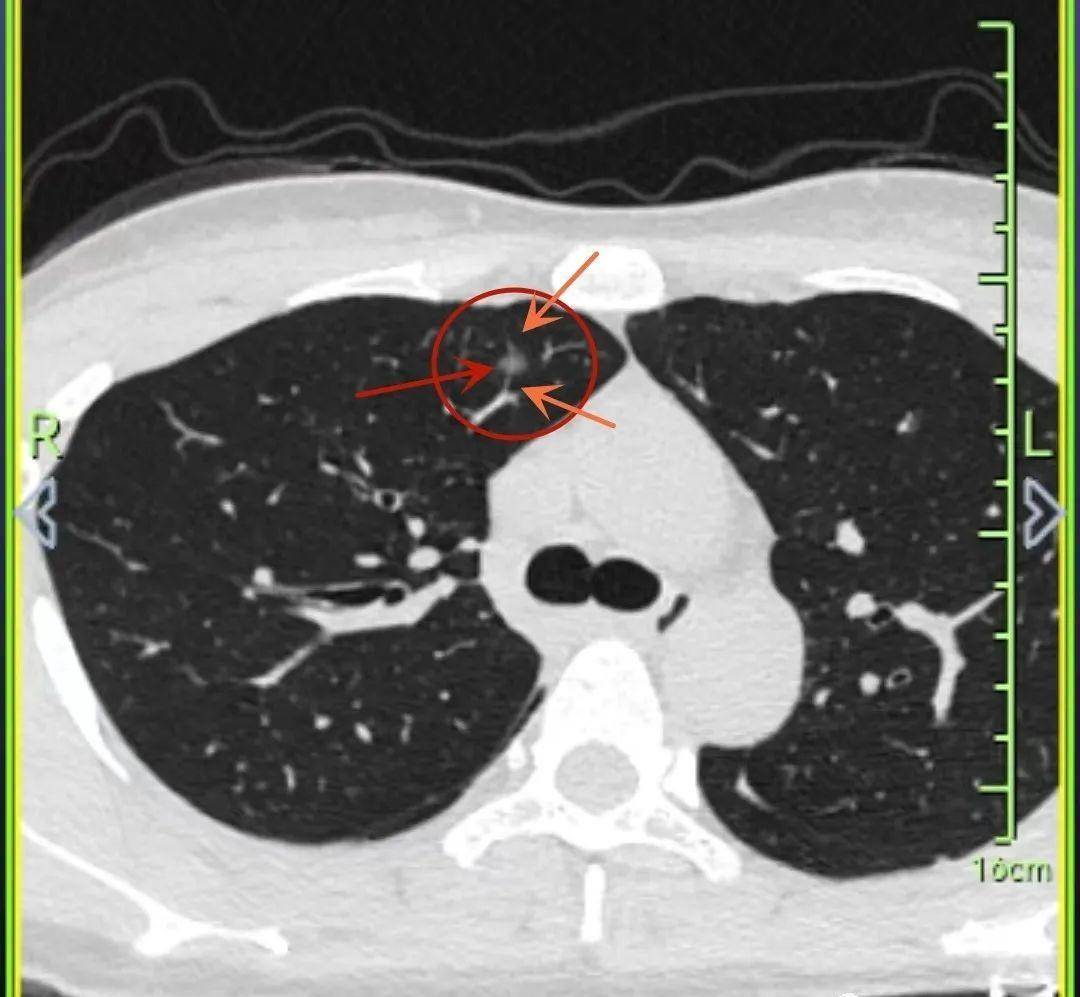

警惕可能漏诊的早期肺癌肺部磨玻璃结节伴空泡型